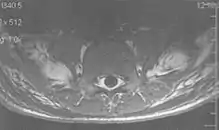

A motion artifact is one of the most common artifacts in MR imaging.[2] Motion can cause either ghost images or diffuse image noise in the phase-encoding direction. The reason for mainly affecting data sampling in the phase-encoding direction is the significant difference in the time of acquisition in the frequency- and phase-encoding directions.[1] Frequency-encoding sampling in all the rows of the matrix (128, 256 or 512) takes place during a single echo (milliseconds). Phase-encoded sampling takes several seconds, or even minutes, owing to the collection of all the k-space lines to enable Fourier analysis. Major physiological movements are of millisecond to seconds duration and thus too slow to affect frequency-encoded sampling, but they have a pronounced effect in the phase-encoding direction. Periodic movements such as cardiac movement and blood vessel or CSF pulsation cause ghost images, while non-periodic movement causes diffuse image noise (Fig. 1). Ghost image intensity increases with amplitude of movement and the signal intensity from the moving tissue. Several methods can be used to reduce motion artifacts, including patient immobilisation, cardiac and respiratory gating, signal suppression of the tissue causing the artifact, choosing the shorter dimension of the matrix as the phase-encoding direction, view-ordering or phase-reordering methods and swapping phase and frequency-encoding directions to move the artifact out of the field of interest.[1]